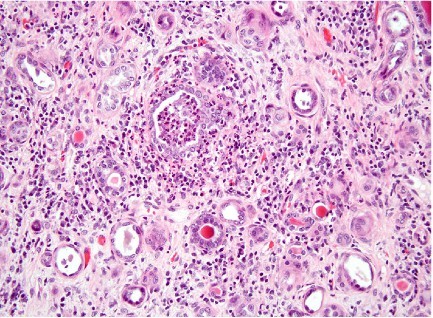

A 32 year old female presents to emergency room with fevers, shaking chills, and flank pain and tenderness. Based on the histology below, what is her diagnosis and treatment? What scenarios would require hospitalization?

Acute pyelonephritis

Path:

Symptoms:

Management:

* Untreated cases can lead to chronic pyelonephritis